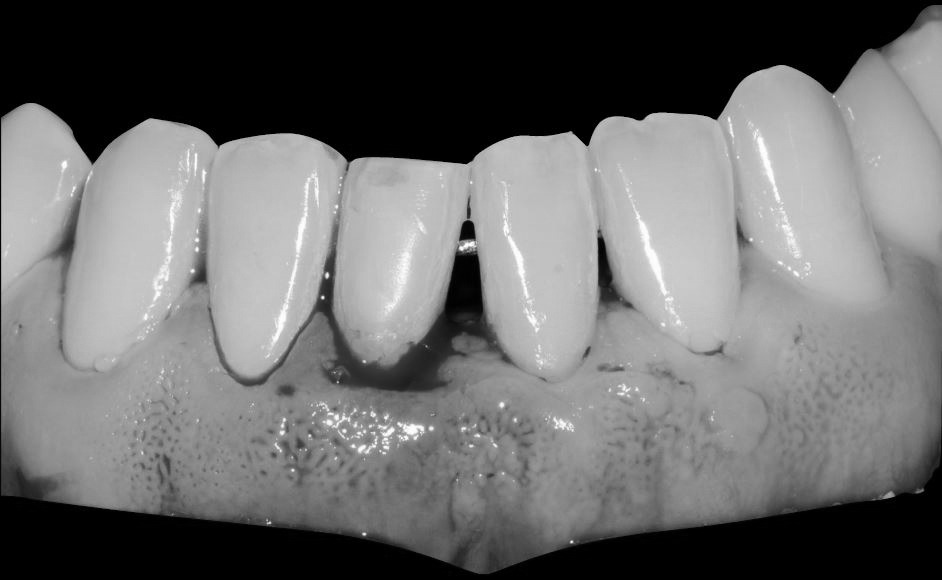

Exploración intraoral inicial:

Objetivos periodontales: Regeneración osea guiada con bioss collagen y emdogain.

- Eliminar tejido necrótico. Regeneración periodontal cemento, ligamento y hueso

- Mejora de la estabilidad y soporte óseo

- Estabilidad periodontal y reducción de la movilidad

Profilaxis mediante airflow y descontaminación periodontal. Más ferulización periodontal

Fotografías del proceso: